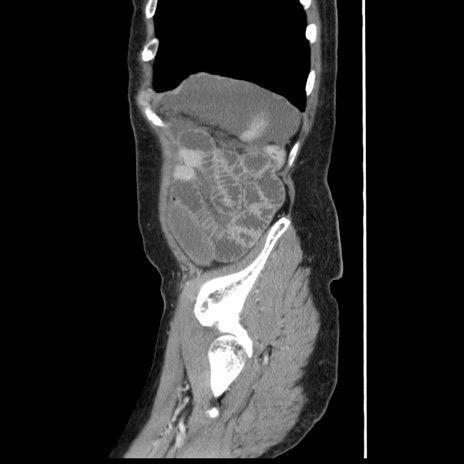

症例1(矢状断像)

【症例】80歳代女性

【主訴】腹痛

【現病歴】8時間前から腹痛あり来院。

【既往歴】糖尿病、脂質異常症、子宮体癌にて子宮全摘術

【身体所見】意識清明・会話良好だが腹痛で苦悶様、全腹部にわたって反跳痛と圧痛あり

【データ】WBC 13600、CRP 0.14、LDH 224、CK 90